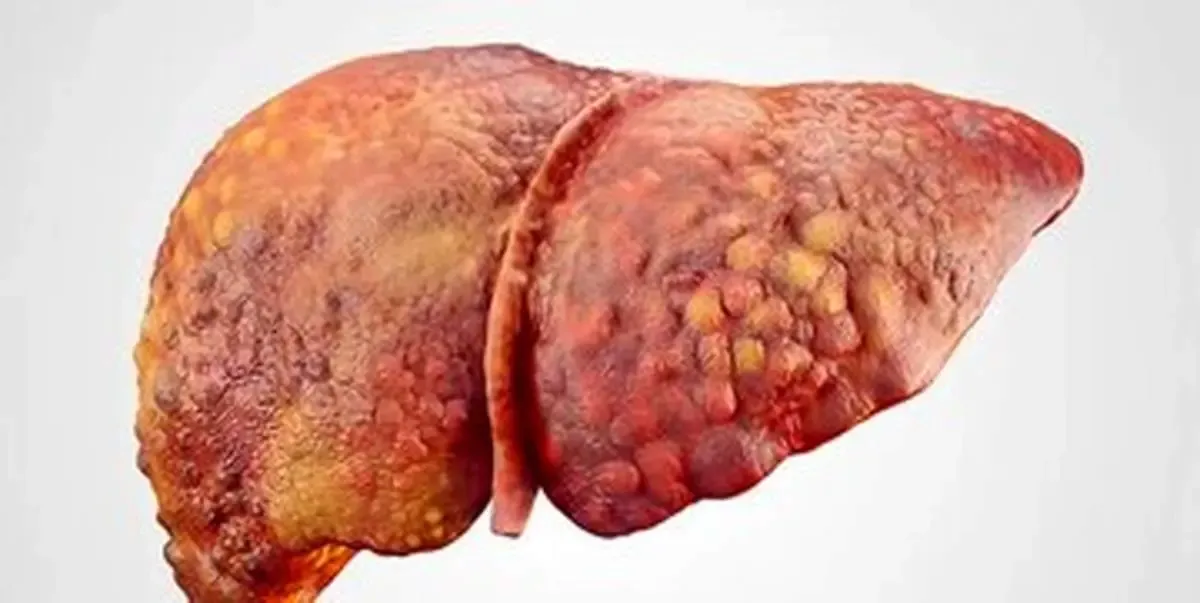

به گزارش آرمان ملی آنلاین؛ نتایچ تحقیق حاکی از این مورد است که مصرف بیش از حد نوشیدنیهای مصنوعی شیرین شده، خطر ابتلا به بیماری کبد چرب غیر الکلی را افزایش میدهد و شامل دادههای ۱۳۶هزار و ۲۷۷ شرکتکننده بدون سابقه بیماری کبدی و بر تأثیر نوشیدنیهای شیرین شده با قند، نوشیدنیهای شیرین شده مصنوعی و آب میوه خالص بر توسعه بیماری کبد چرب غیر الکلی متمرکز بود.

یافتهها نشان داد که مصرف نوشیدنیهای شیرین شده با قند، نوشیدنیهای شیرین شده مصنوعی و آب میوه خالص همگی با خطر بیماری کبد چرب غیر الکلی مرتبط هستند.

مصرف نوشیدنیهای شیرین شده مصنوعی ارتباط معنادارتری با خطر ابتلا به بیماری کبد چرب غیر الکلی نشان داد. در مقابل، مصرف آب میوه خالص ارتباط ضعیفی با این بیماری دارد.

نتایج این تحقیق یک روند نگرانکننده را برجسته میکند که نشان میدهد مصرف بیش از حد نوشیدنیهای مصنوعی شیرین ممکن است به پیشرفت بیماری کبد چرب غیر الکلی کمک کند.